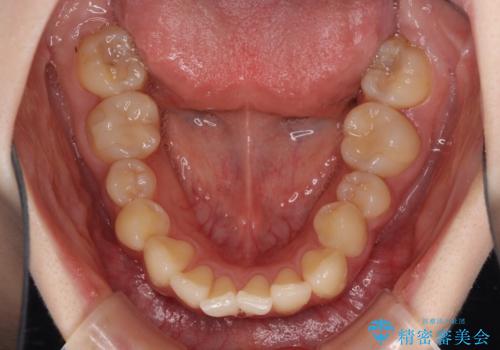

デコボコ歯列をきれいに インビザラインによる矯正治療

- 上下歯列全体のデコボコを気にして来院された患者様です。

主に下顎歯列全体の後方移動とIPR(歯と歯の間を削る)によってデコボコが解消するように設計し、インビザラインにより治療を行うこととしました。